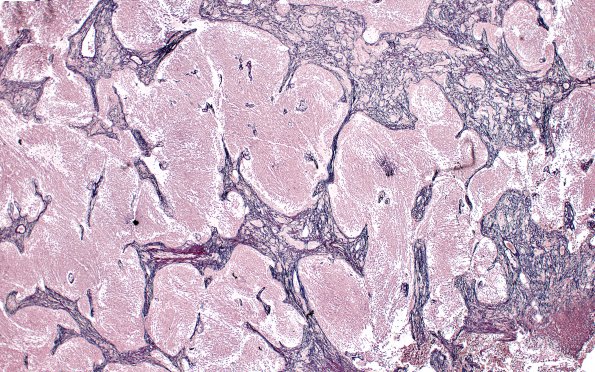

Washington University Experience | NEOPLASMS (EMBRYONAL) | Medulloblastoma, Histologically Defined | Extensive Nodularity (MBEN) | 5E2 Medulloblastoma, Desmoplastic (Case 5) Retic 4X 12

The internodular proliferative areas are reticulin-rich compared with the nodular pale areas which are distinctively devoid of reticulin.